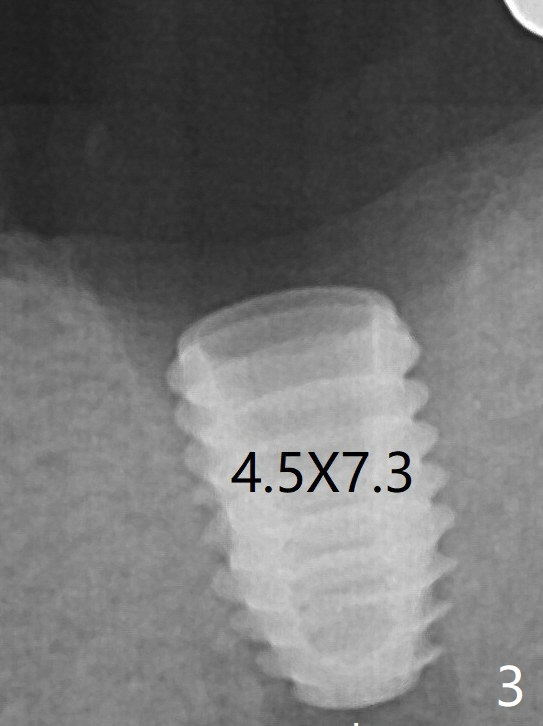

A 4.5x7.3 mm implant is initiatlly placed (Fig.3). The coronal defect is filled with allograft (Fig.4 *) following further placement of the implant. There is reorganized bone coronal to the healing screw 4 months postop (Fig.6), which is confirmed in uncovering. The overlying bone should be removed thoroughly for complete abutment seating.